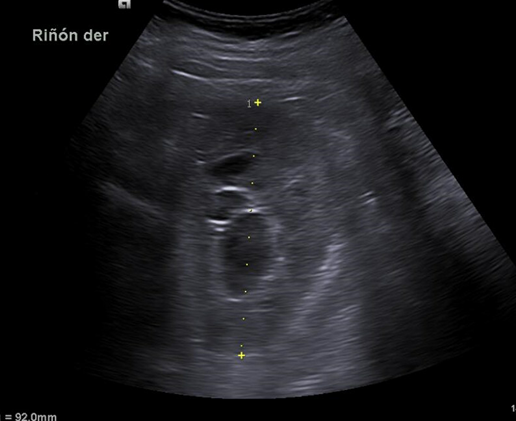

Mujer de 69 años sin antecedentes de interés que acude al centro de salud por presentar dolor en fosa renal derecha de varios días de evolución con sensación distérmica asociada. Exploración: abdomen anodino con puñopercusión renal derecha positiva. Se realiza ecografía renal clínica urgente.

Hallazgos ecográficos

Riñón derecho 9,9 cm con morfología y ecogenicidad conservada. Presenta hidronefrosis grado III. No se identifica causa obstructiva.